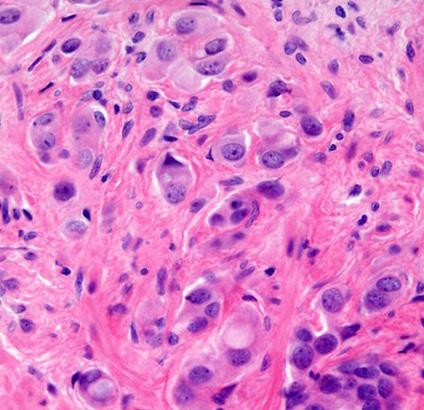

Anew UCLA study has found that artificial intelligence could help doctors identify prostate cancer patients most likely to benefit from targeted treatment that removes cancer while sparing healthy tissue, according to a UCLA-led study published Tuesday.

Researchers evaluated the new Unfold AI software that uses data from MRIs and biopsies to generate a detailed 3D map of prostate tumors. The study found that the AI technology's measurements of tumor size — compared with relying solely on tumor grade or prostate-specific antigen levels — significantly improved doctors' predictions of successful treatment.

"By using AI to measure the size of a man's prostate tumor more precisely, we can better predict who is likely to be cured with focal therapies like partial gland cryoablation," Dr. Wayne Brisbane, assistant professor of urology at UCLA's David Geffen School of Medicine,

said in a statement.

The study tested whether Unfold AI's tumorvolume mapping would aid doctors in predicting a patient's likelihood for successful outcomes from a treatment called "partial gland cryoablation," a minimally invasive procedure that freezes and eradicates only cancerous areas of the prostate instead of removing or irradiating the entire gland. The treatment minimizes damage to vital areas, which reduces side effects in an effort to maintain patients' quality of life, researchers found. Current methods of predicting treatment success — tumor grade and PSA levels — often underestimate tumor size can miss smaller cancerous areas, often leading to incomplete treatment and cancer recurrence.

"The study marks an important advance in integrating AI into prostate cancer treatment decisionmaking, offering the potential for more personalized prostate cancer care,"

TBrisbane said.

Although the findings are promising, researchers emphasized the need for broader trials to validate the results.

“Such a method has not been previously available," Dr. Leonard Marks, professor and deKernion Endowed Chair in Urology UCLA's medical school, said in a statement. "It's important because tumor volume is a major determinant of treatment success or failure."

Marks, who is also a member of the UCLA Health Jonsson Comprehensive Cancer Center and senior author of the study, added, "Using AI to predict tumor volume and shape gives a clearer picture and could help choose better candidates for focal cryotherapy.”

Unfold AI was developed by researchers at UCLA and Avenda Health.

The study was published in BJUI Compass, a peerreviewed medical journal specializing in urology, and is available online at pmc. ncbi.nlm.nih.gov/articles/ PMC11771490.

Prostate cancer cells. | Image courtesy of Jennifer Gordetsky and Jonathan Epstein/Wikimedia Commons (CC BY 4.0)